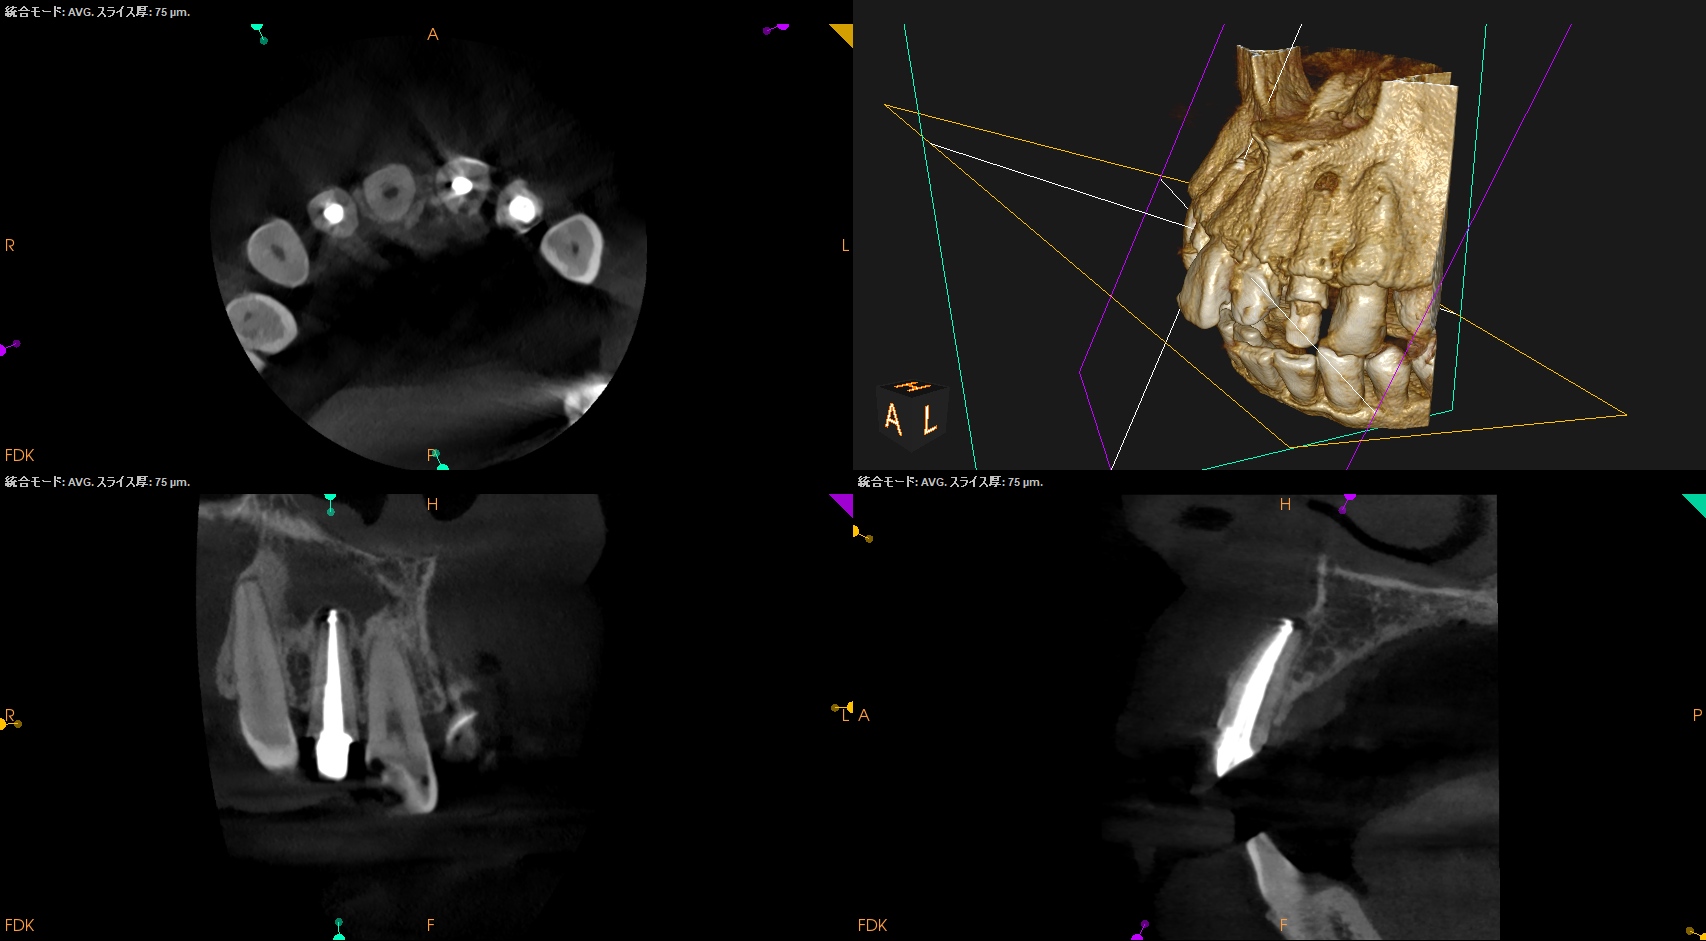

CBCT(2025.1.16)

#7

頬側皮質骨が消失している。

これが圧痛の原因だろう。

#10

#10も#7に同じである。

根管形成・当該部位への根管充填がほぼなされていないように見えることから, 再根管治療へ移行した。

さておき、根充+支台築造後にPA, CBCTを撮影した。